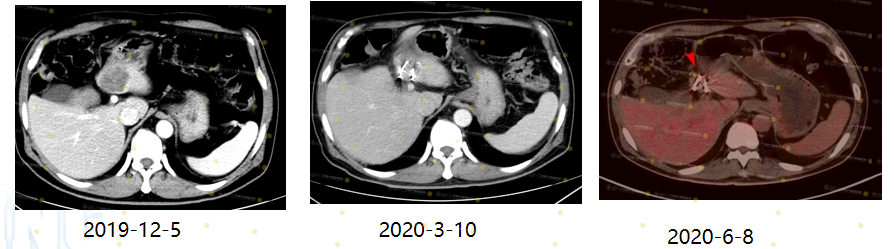

(Lưu ý: Bệnh nhân ung thư trực tràng từ năm 2019)

Sau khi điều trị bằng liệu pháp sinh học, tổn thương di căn phổi của bệnh nhân đã đạt đáp ứng hoàn toàn (CR).

Trong quá trình theo dõi, bệnh nhân xuất hiện tổn thương di căn gan mới, được đánh giá là kháng thuốc thứ phát.

Dựa trên tình trạng này, bệnh nhân được chỉ định cấy hạt phóng xạ I-125 để kiểm soát tổn thương tại gan.

Mục tiêu điều trị là kéo dài kiểm soát bệnh và hướng tới trạng thái không còn bằng chứng ung thư (NED).